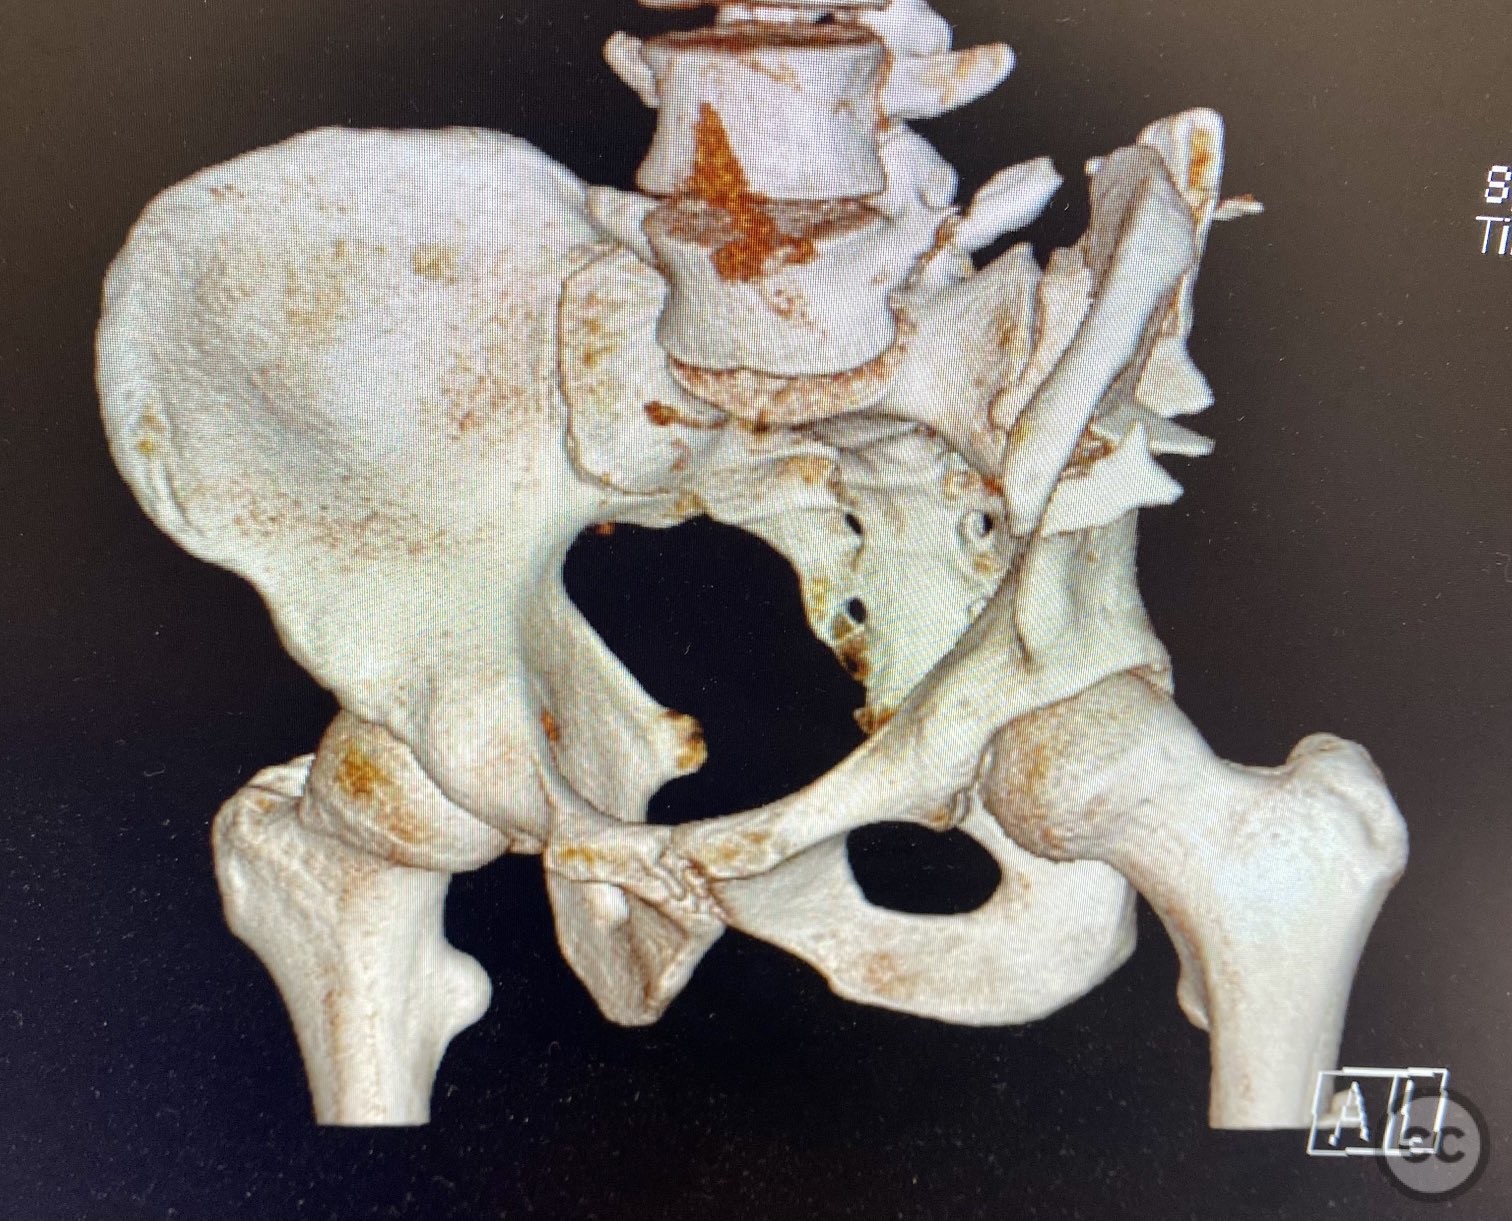

Clinical and radiological findings:  A patient sustained a high-energy injury resulting in an open, comminuted fracture of the iliac wing, sparing the pelvic ring. Associated injuries included spine, rib, and femur fractures. Initial radiographs and axial CT imaging demonstrated significant comminution of the iliac wing with intraosseous air densities indicative of an open wound. No pelvic ring disruption was identified. AO/OTA classification: 61-A2. The presence of multiple associated injuries is consistent with a direct lateral load mechanism.

Anatomical surgical approach:  A direct lateral approach to the os ilium was performed, with incision centered over the iliac crest. Subperiosteal dissection was carried down to expose the fractured segments of the ala ossis ilii. The open wound was incorporated into the exposure for thorough irrigation and debridement. Fracture fragments were anatomically reduced and stabilized with interfragmentary lag screws placed between the inner and outer tables of the ilium.

The comminuted nature of the fracture required careful sequential reduction of multiple small fragments. Given the open nature of the injury and risk of contamination, meticulous irrigation and debridement were performed both through the traumatic wound and via surgical exposure. Lag screw fixation was selected to minimize hardware prominence and reduce surface area for potential infection. The traumatic wound was closed primarily with sutures due to satisfactory soft tissue condition; surgical incisions were closed in layers over drains.